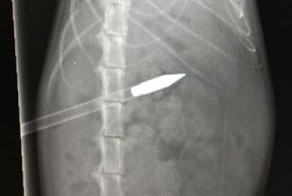

Смотрители зоопарка в городе Чэнду отправили черепаху по кличке Дабао в госпиталь на рентген, чтобы выяснить, почему она постоянно пребывает в полулетаргическом состоянии.

"Мы были удивлены, когда узнали, что внутри у нее находятся 14 яиц", - отмечает господин Ву, администратор зоопарка. - Мы заподозрили, что из-за такого большого количества яиц она не может разродиться".

Эта процедура заняла у медиков более двух часов. Панцирь открыли, разрезали живот, извлекли из него 14 яиц и затем вновь запечатали панцирь с помощью эпоксидной смолы.